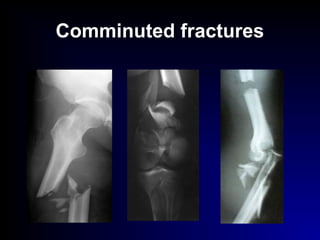

Comminuted fractures